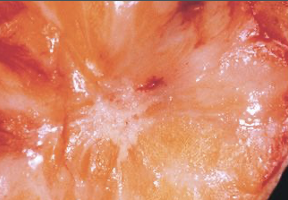

what is this condition of the breast capsule

breast implant associated anaplastic large cell lymphoma